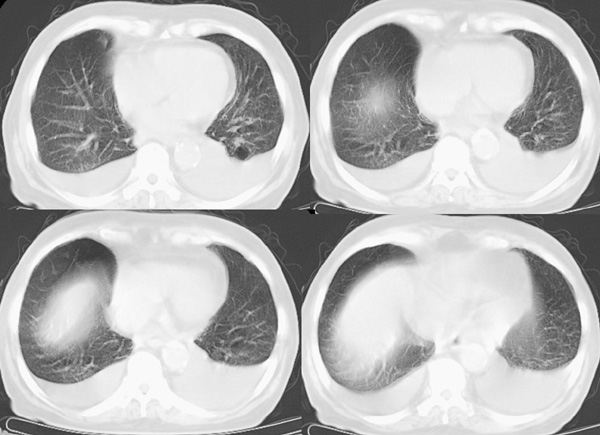

以下是引用panyishengct在2008-5-19 21:48:00的发言:[br]左侧胸壁脂肪瘤;肺部还是考虑肺水肿,胸腔积液。 [br] [br]左肺门见一团状影,纵隔见淋巴结,建议治疗后复查,以排外中央型肺癌

以下是引用形影不离在2008-5-19 21:13:00的发言:[br]左侧胸壁脂肪瘤;肺部还是考虑心衰并肺水肿,胸腔积液。